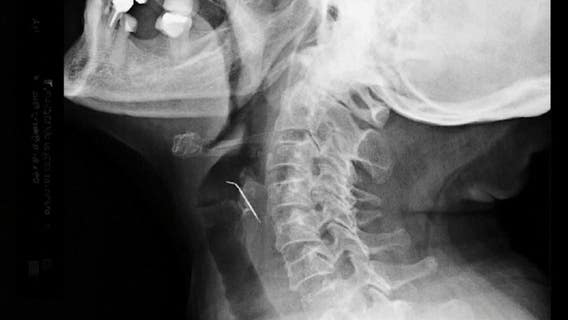

Woman eating pork rinds accidentally swallows nail

A South American woman found herself in a hospital emergency after inadvertently ingesting a nail that mysteriously found its way into her packet of pork rinds.